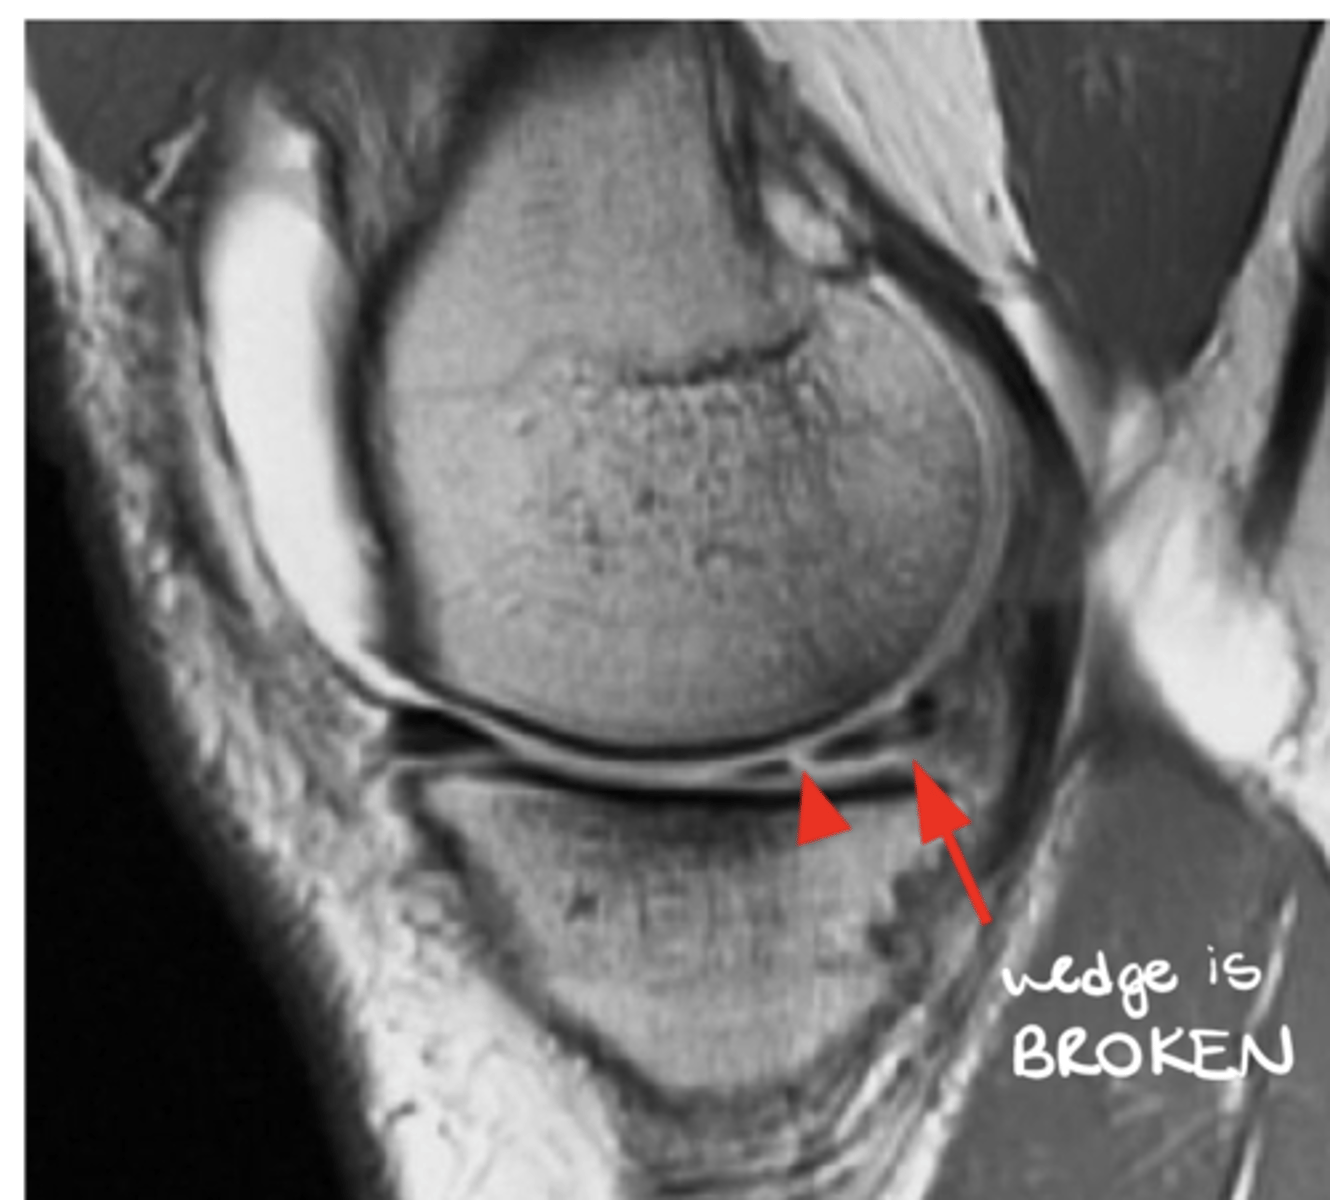

Meniscus tear (the meniscus should look like a wedge)

Define the pathology.

Meniscus tear